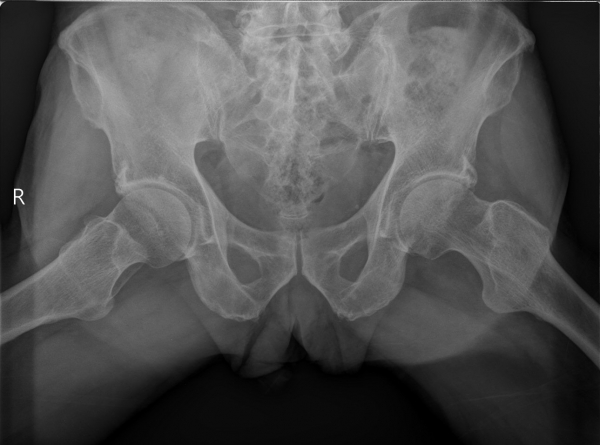

[¾ûµ¢ÀÌ] °í°üÀý Ãæµ¹ÁõÈıº¿¡ÀÇÇÑ È°¾×¸·¿° ÁÖ»çÄ¡·á

´Ü¼ø¹æ»ç¼±°Ë»ç